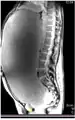

-

MRI giant serous cystadenoma of ovary -

MRI giant serous cystadenoma ovary